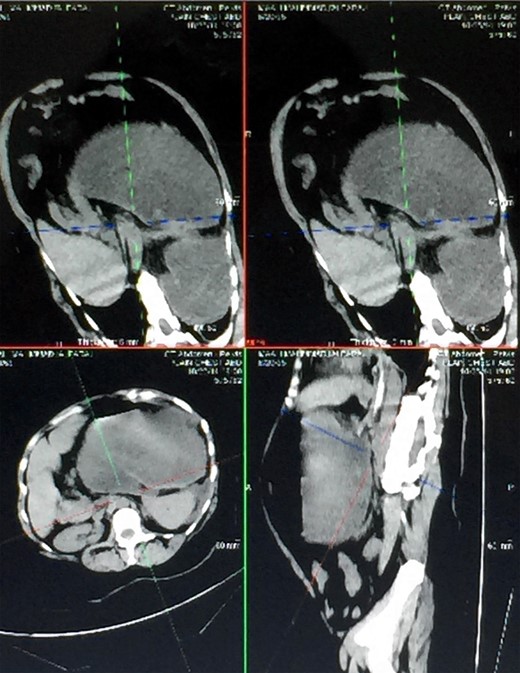

Two days prior to her admission, she had undergone upper gastrointestinal endoscopy for the same complaint in another center that revealed a dilated gastric lumen with herniation of the distal stomach, pylorus and first part of the duodenum into the left hemi-thorax (Fig. 2). She refused treatment and left against medical advice. She presented to our emergency department with worsening symptoms. Resuscitation was commenced with immediate nasogastric decompression, intravenous hydration and analgesia, proton-pump inhibitors and electrolyte replacement. A double contrast-enhanced computed tomography (CT) scan of the chest and the abdomen demonstrated a large diaphragmatic defect (7 × 7 cm) and a left diaphragmatic hernia containing a dilated stomach, suggestive of a gastric outlet obstruction (Fig. 3). A water-soluble gastrografin meal was performed, showing an intra-thoracic, mesentero-axial gastric volvulus (Fig. 4).

Different views of a double contrast-enhanced CT scan showing a left diaphragmatic hernia with an acute dilated stomach.